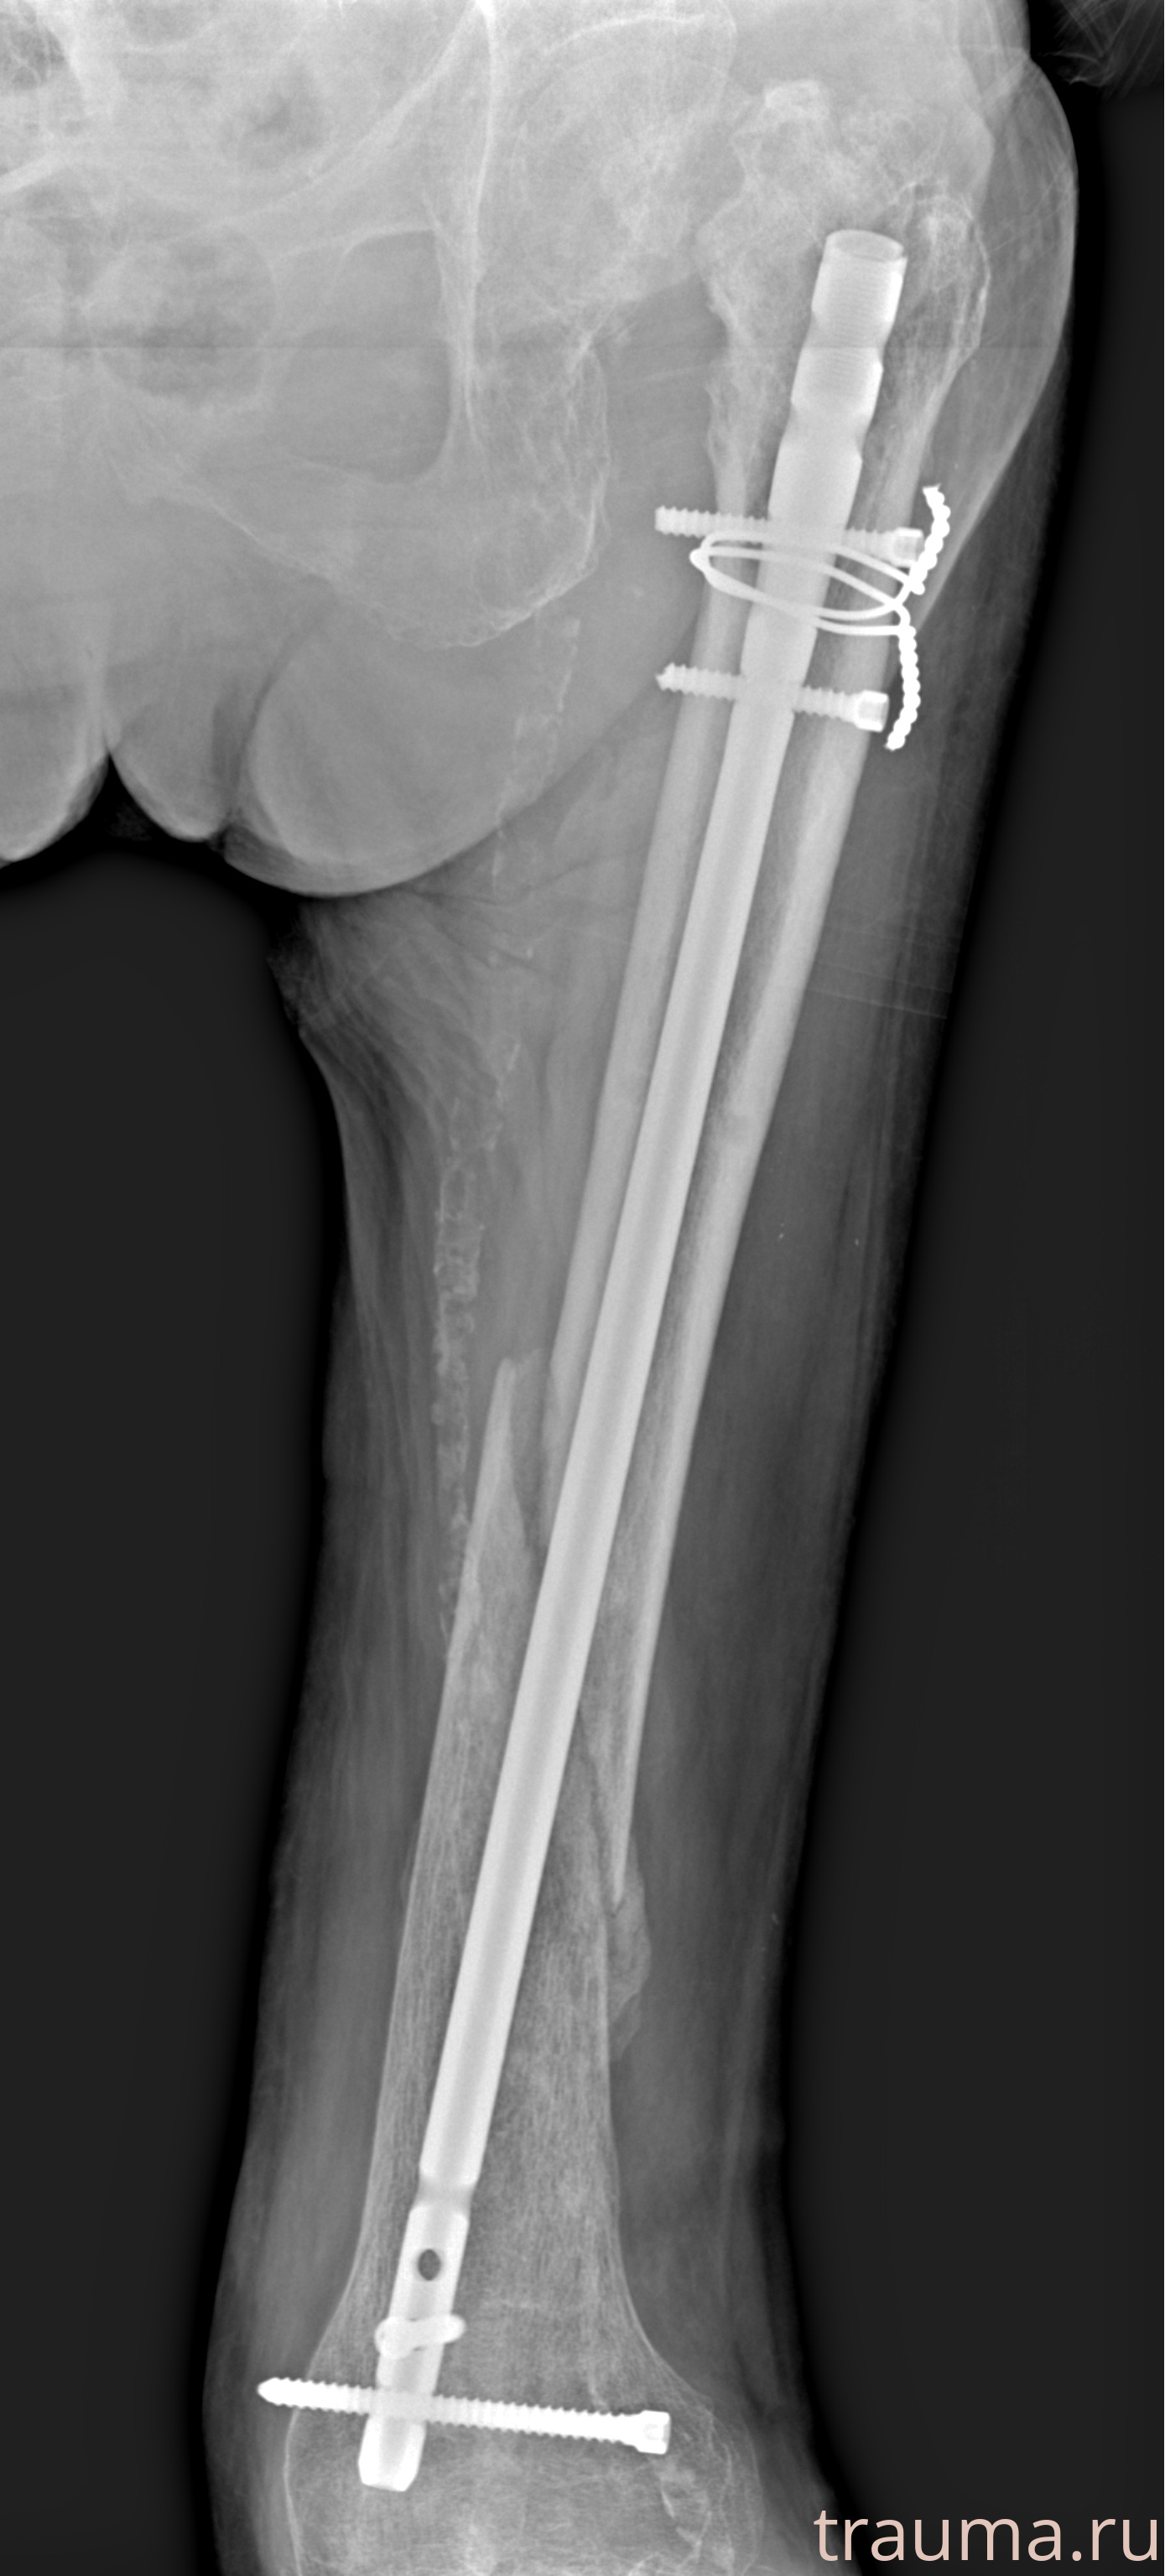

Рентгенограммы

Рентген на дому: по вашему адресу приезжает врач-рентгенолог, травматолог-ортопед с мобильным рентгеновским аппаратом, проводит диагностику травмы или заболевания, делает необходимые рентгенограммы, дает рекомендации по дальнейшему лечению. Получить качественные снимки в домашних условиях возможно благодаря уникальной методике, разработанной МосРентген Центром для института  Склифосовского